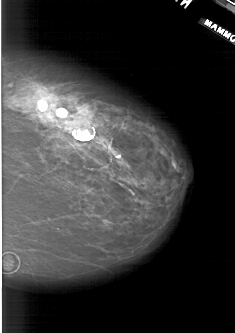

A_1941_1.LEFT_MLO

LEFT_MLO LINES 5986 PIXELS_PER_LINE 4276 BITS_PER_PIXEL 12 RESOLUTION 43.5 OVERLAY

FILE: A_1941_1.LEFT_MLO.OVERLAY

TOTAL_ABNORMALITIES 1

ABNORMALITY 1

LESION_TYPE CALCIFICATION TYPE PLEOMORPHIC DISTRIBUTION CLUSTERED

ASSESSMENT 4

SUBTLETY 2

PATHOLOGY BENIGN

TOTAL_OUTLINES 1

BOUNDARY